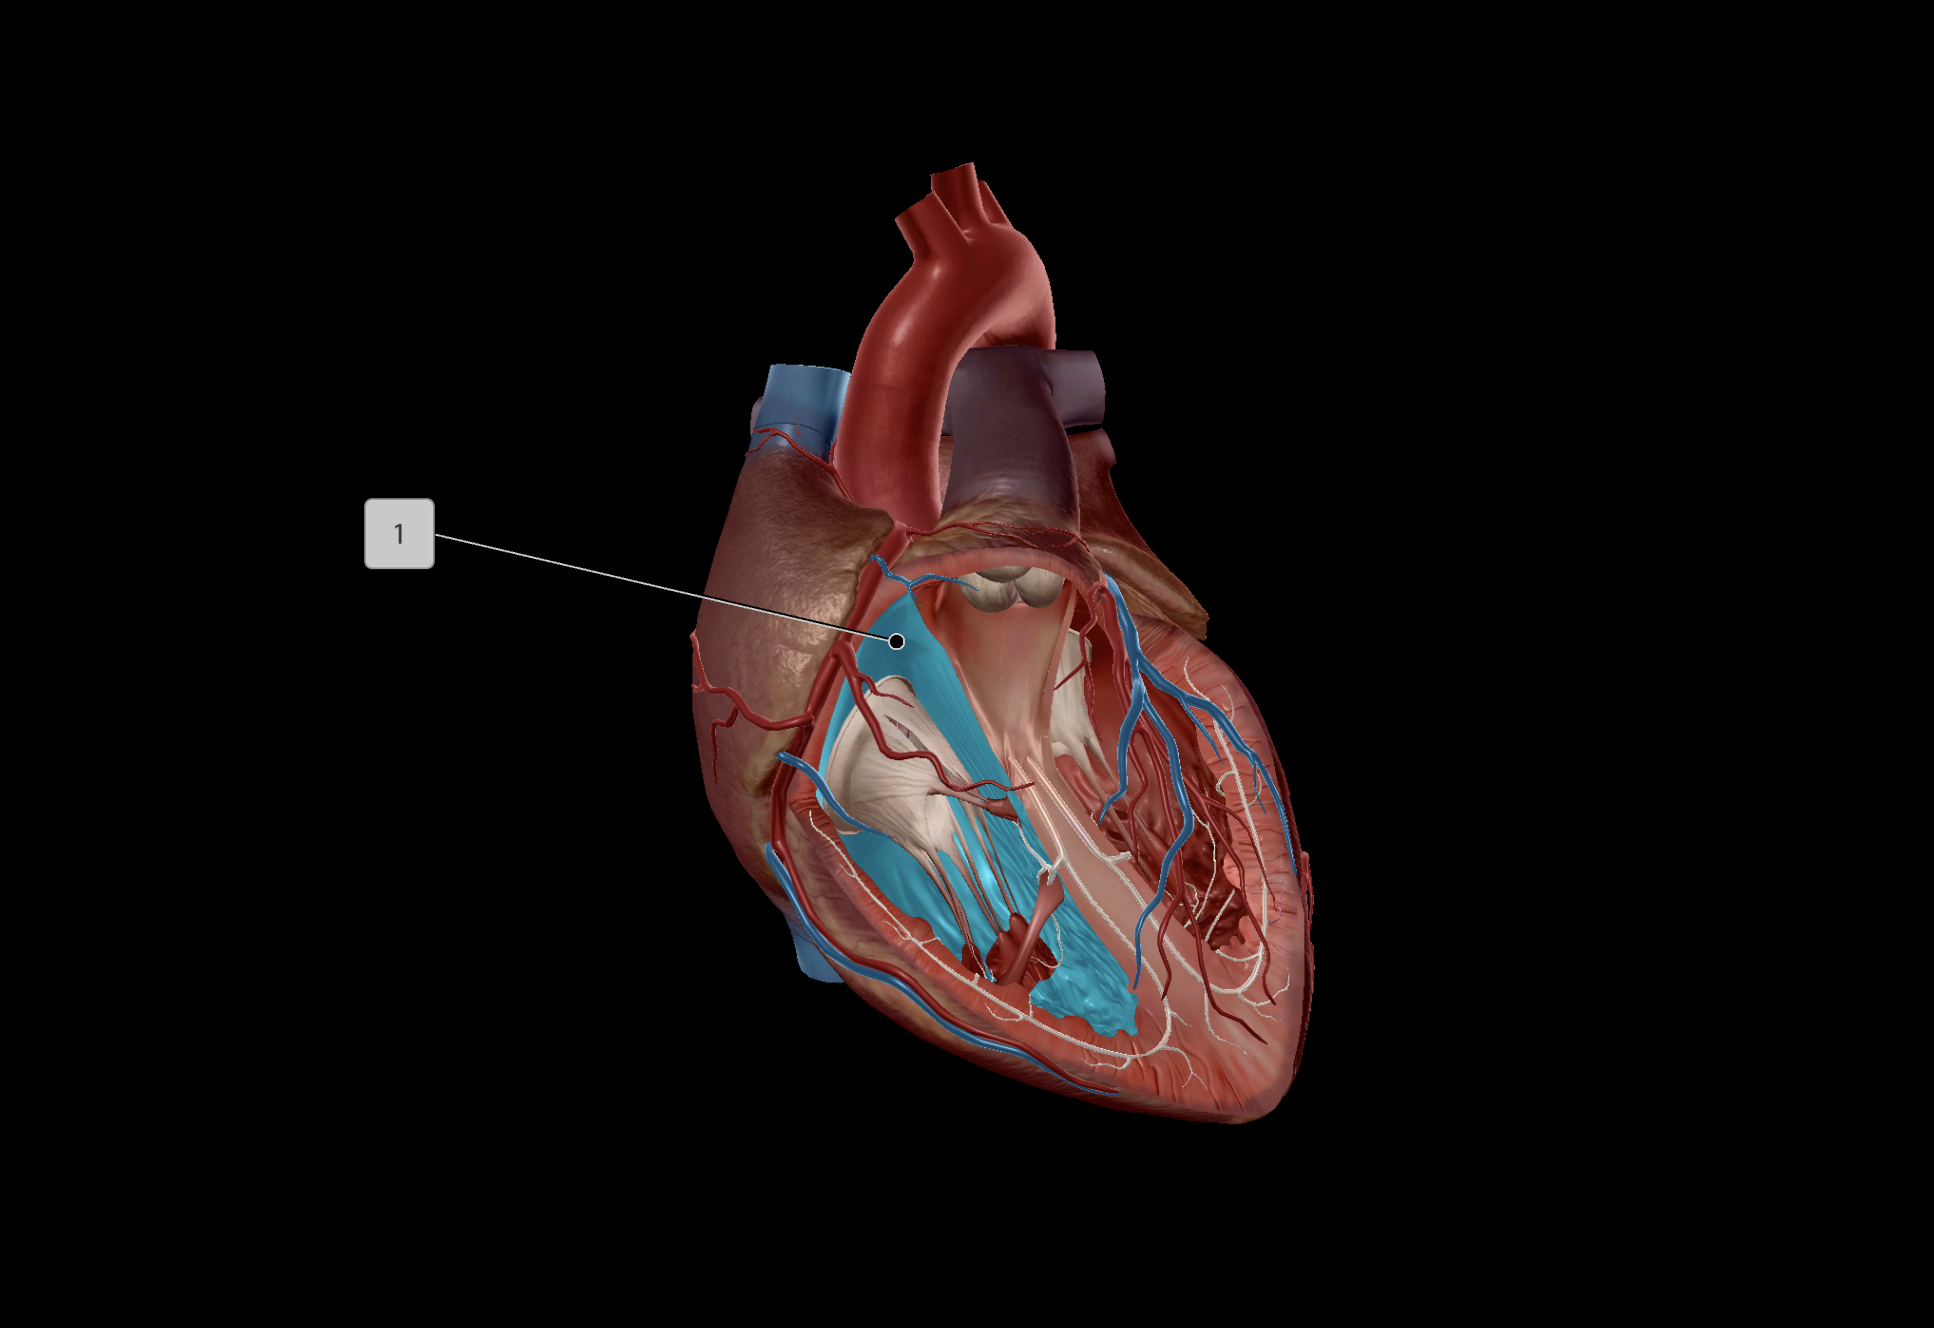

Tricuspid Valve

Bicuspid Valve

Aortic Valve

Papillary Muscle

Pulmonary Valve

Interventricular Septum

Chordae Tendineae

AV Node

SA Node

Bundle of His

Interatrial Septum